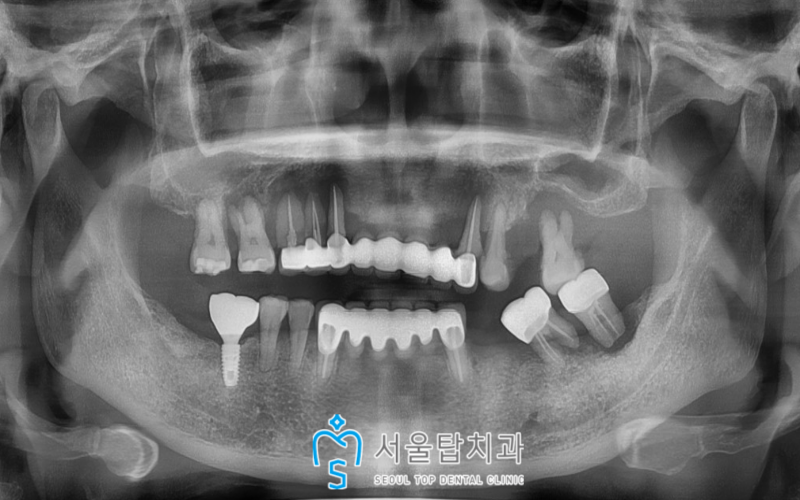

오늘 소개해 드릴 분께서는

50대 여성분으로,

전체적으로 치아가 많이 흔들려

식사하시기 힘드시다며

치료를 위해 시흥치과를 찾아주셨는데요.

파노라마 사진을 촬영해 보니

전체적으로 치조골 소실이 심하여

다수의 치아에

흔들림도 심한 상태였습니다.

위턱의 전체 치아와

왼쪽 아래턱의 어금니 두 개는

더 이상 살리기 어려워 발치가 필요했으며

기존 상실된 치아 부위를 포함하여

임플란트 식립을 진행하기로 하였습니다.